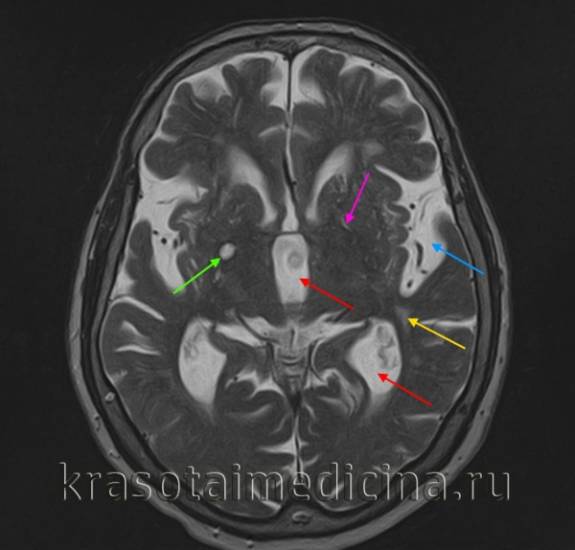

| Диагностика | КТ, МРТ головного мозга, УЗИ сосудов шеи, ангиография. | Позволяет точно определить размер, локализацию и характер повреждения. |

- компьютерную томографию (КТ) или магнитно-резонансную томографию (МРТ);

Современные технологии визуализации, такие как магнитно-резонансная томография (МРТ) и компьютерная томография (КТ), позволяют более точно диагностировать ишемические очаги и оценивать их размеры и локализацию. Это, в свою очередь, способствует более раннему началу лечения и повышению его эффективности. Исследования в области функциональной МРТ также открывают новые горизонты для понимания того, как ишемия влияет на работу различных участков мозга.